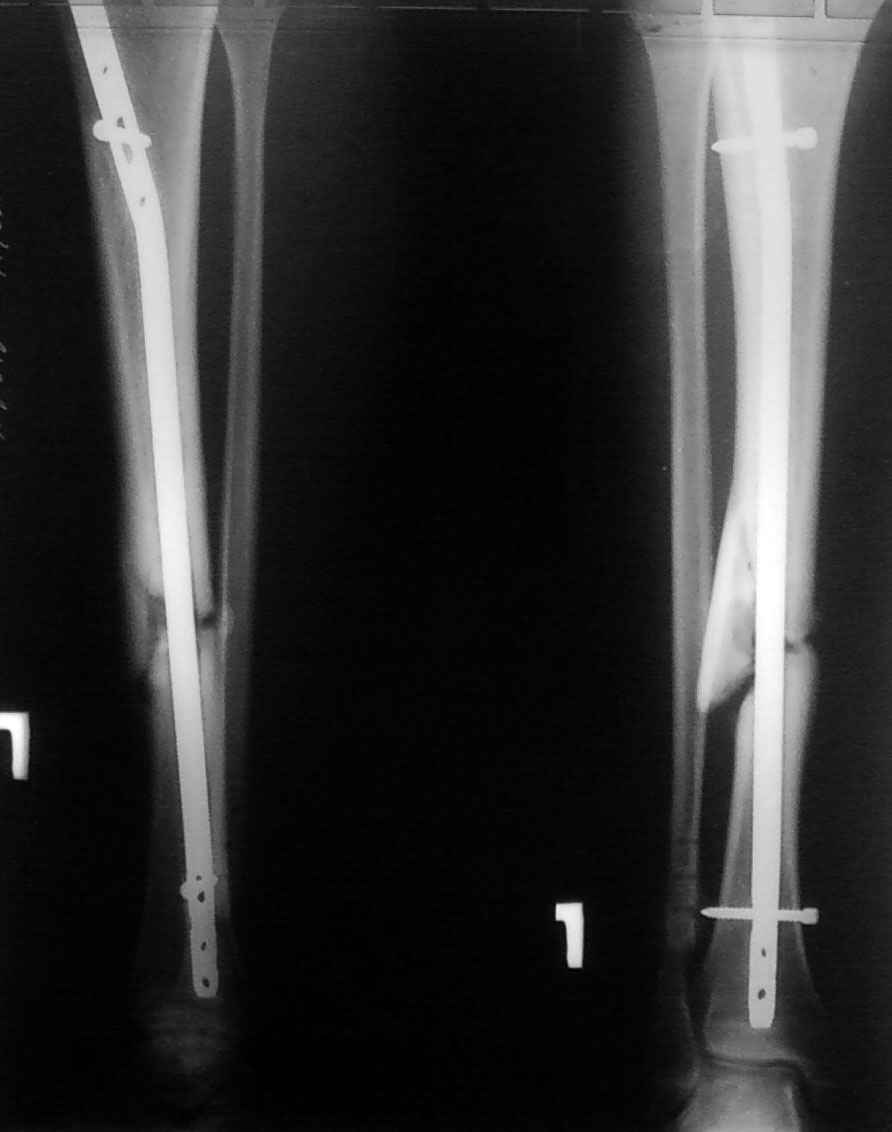

несросшийся перелом голени после БИОС |

Пациент 24лет травма в мае 2009г, сбит а/м. диагноз: вторично-открытый перелом правой м/б кости в н/3, оскольчатый перелом б/б кости справа. Рана по наружной поверхности 2*1 см. В первые сутки выполненно ПХО открытого перелома м/б кости остеосинтез 1/3трубчатой пластины (синтез выполнен из-за того, что проксимальный отломок мог вызвать угрозу внутреннего пролежня) и БИОС б/б кости стерженем Chm в статическом варианте. П/о период без осложнений. Через 2 месяца выполнена динамизация. Ходил без дополнительной опоры. Через 6месяцев обратился с жалобами на боль в н/3 голени. На контрольном снимке сломана пластина 1/3 трубки, вполнена операция - удаление пластины. Обратился сегодня с жалобами на боли в области концов стержня (в/3 и н/3), боль при ходьбе. Что делать?Мы думаем заменить стержень на 11мм (сейчас 9мм) и рассверлить канал с целью освежить зону перелома. СПАСИБО.